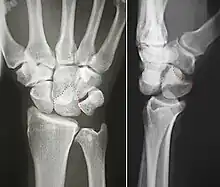

Dislocated lunate